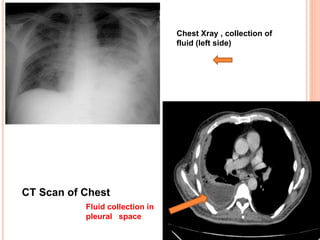

CT Scan of Chest

Fluid collection in

pleural space

Chest Xray , collection of

fluid (left side)

CT Scan ofChest Fluid collection in pleural space Chest Xray , collection of fluid (left side)